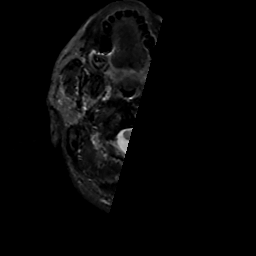

MR Study #14, June 2, 1991 -- Slice #0

[Home][Help][Clinical][Tour 1][Tour 2] Slice 0